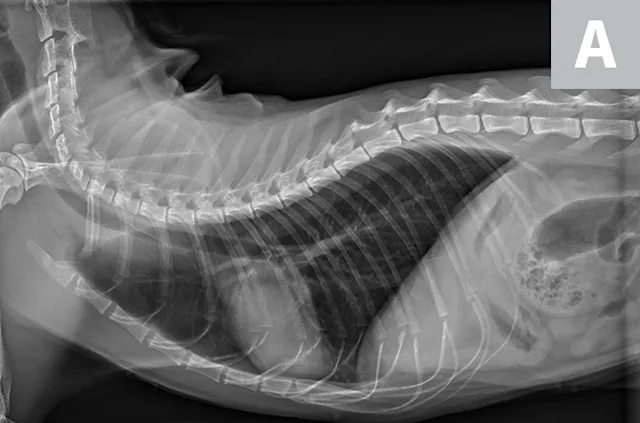

FIGURE 1A

Lateral radiographs of a 2-year-old cat (A) and a 9-year-old cat with increased sternal contact of the cardiac silhouette (B).